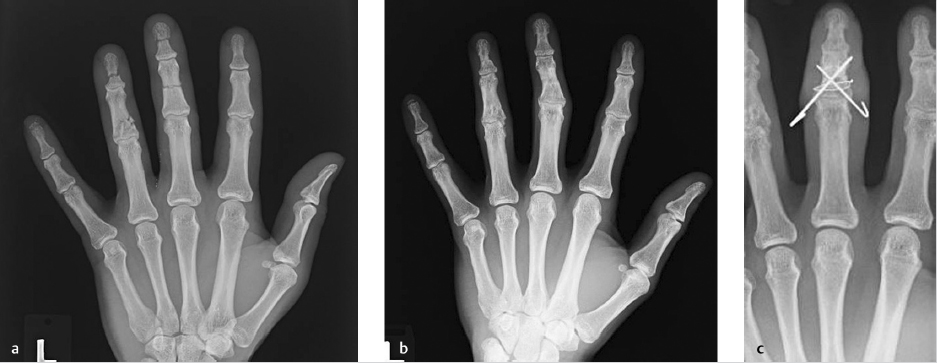

Malunion is the result of a fracture healed with deformity. The bone is stable, but the functional impact is determined by the location, type, and severity of the deformity. Osteotomy allows for deformity correction to achieve acceptable alignment with internal fixation. 1

47.4 Indications

Malunion management is variable and is up to individual surgeon and patient preference, as patients will have different functional requirements and personal desires. 1 While most malunions involve a combination of deformities, usually there is one major component causing functional change and causing surgical consideration. 3 Phalangeal malunions greater than 15 degrees in the sagittal plane or 10 degrees of malrotation that are symptomatic or functionally obstructive may benefit from osteotomy. 1 , 3 Other indications include pain or decreased grip strength. 4

A detailed preoperative evaluation is important. This should include deformity and functional limitation assessment, including investigation of the bone and soft tissues. X-rays of the malunion site will help to determine potential correction sites and need for possible bone graft. 5